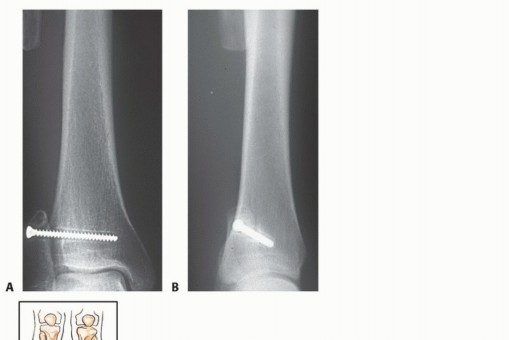

أنواع الاستئصال الجراحي للشظية القريبة

هناك ثلاثة أنواع رئيسية من استئصال الأورام حول الشظية القريبة:

-

الكشط (Curettage):

- الإشارة: يُستخدم للأورام الحميدة العدوانية والأورام الغرنية منخفضة الدرجة المرتبطة بتدمير قشري بسيط وامتداد خارج العظم ضئيل.

- الإجراء: يتم إزالة الورم يدويًا بواسطة مكشطة، ثم تُستخدم مثقاب عالي السرعة لتنظيف جدران تجويف الورم بدقة لضمان إزالة أي مرض مجهري متبقي.

- الحفاظ: يتم الحفاظ على العصب الشظوي المشترك والأوعية الدموية.

-

الاستئصال من النوع الأول (Type I Resection):

- الإشارة: يُستخدم لعلاج الأورام الحميدة العدوانية والأورام الغرنية منخفضة الدرجة التي تسببت في تدمير قشري كبير للشظية القريبة.

- الإجراء: يشمل إزالة الشظية القريبة، وغلاف عضلي رقيق من جميع الأبعاد، وموقع ارتباط الرباط الجانبي الوحشي (LCL). يتم الحفاظ على العصب الشظوي المشترك وفروعه الحركية، ويتم استئصال المفصل الظنبوبي الشظوي داخل المفصل.

- الحفاظ: يتم الحفاظ على العصب الشظوي والشريان الظنبوبي الأمامي عادةً.

يوضح الجدول التالي الهياكل التشريحية التي يتم إزالتها مع أنواع الاستئصال المختلفة للشظية القريبة:

| نوع الجراحة | موقع ارتباط الرباط الجانبي الوحشي | الشريان الظنبوبي الأمامي | العصب الشظوي |

|---|---|---|---|

| الكشط | سليم | سليم | سليم |

| استئصال من النوع الأول | مُزال | سليم | سليم |

| استئصال من النوع الثاني | مُزال | مُزال | مُزال |